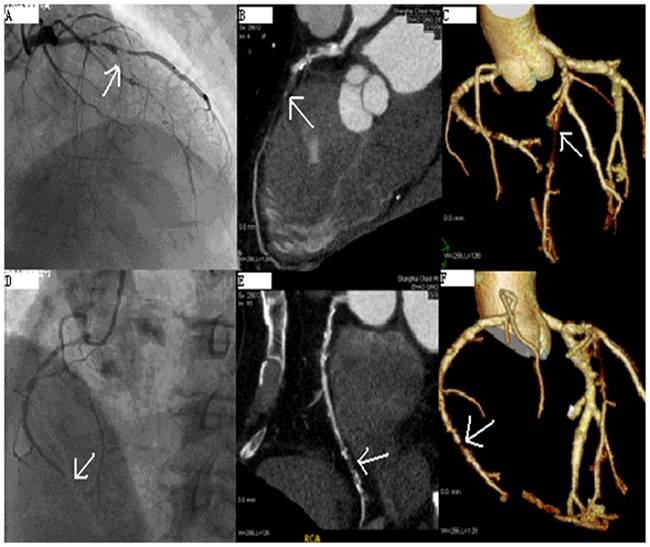

Coronary computed tomography angiography (CCTA) adalah modalitas pemeriksaan radiologi yang semakin banyak diterima sebagai pemeriksaan lini pertama untuk evaluasi nyeri dada. Pada penyakit arteri koroner (coronary artery disease/CAD), CCTA dapat menunjukkan tahap-tahap aterosklerosis, mulai dari pembentukan, progresi, hingga ruptur plak. Coronary artery disease (CAD) stabil adalah kondisi yang ditandai episode-episode iskemia reversibel yang biasa dihubungkan dengan nyeri dada transien.

Secara tradisional, untuk menentukan beratnya derajat CAD diperlukan evaluasi stenosis arteri koroner dengan pemeriksaan invasive coronary angiography (ICA). Saat ini, pedoman klinis mengenai manajemen CAD stabil merekomendasikan pasien dengan pre-test probability sedang (15-85%) terhadap CAD signifikan untuk menjalani evaluasi yang bersifat noninvasif, salah satunya coronary computed tomography angiography (CCTA).[1,2]

Bukti ilmiah yang tersedia menunjukkan bahwa akurasi CCTA lebih baik dibandingkan angiografi konvensional. Pemeriksaan ini memiliki negative predictive value (NPV) yang tinggi yaitu 83-99%, serta negative likelihood ratio 0,02. Hal ini menandakan bahwa CCTA cukup baik digunakan untuk eksklusi penyakit arteri koroner obstruktif atau iskemia miokard.